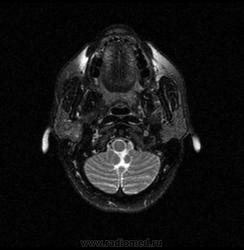

06.06.2011 МРТ - головы и шеи.

Пацентка 36 лет, с жалобами на припухлось в околоушной области справа.

В глубокой доле  правой околоушной железы  на фоне неизмененной паренхимы зона  гетерогенного по Т2, гипоинтенсивного по Т1  с единичными гиперинтенсивными включениями.При контрастировании- накопление контраста диффузное неоднородное и по периферии.Рискну предположить злокачественное образование ( аденокарцинома) с низкой степенью злокачественности( есть капсула, экспансивный рост).Сильно не расстреливайте.

Проблема в том, что перед челюстно-лицевым хирургом стоит распространенность любого объемного процесса, в данном случае все упирается в возмможную травму лицевого нерва и конечно же с дальнейшим его парезом, а ведь женщина  еще молодая. Образование имеет тонкостенную оболочку, по структуре неоднородно, с наличием кальцината, при этом МР-сигнал от окружающих анатомических структур(как костных так и мышечных) не изменен, т.е. об инфильтративном росте речи не идет, в какой то степени доброкачественное. В конкретном случае лицевой нерв с ретромандибулярной веной просто несколько оттеснен.

По гистологии аденома околоушной слюнной железы, но после удаления пока сохраняется парез лицевой мускулатуры, возможно временный.